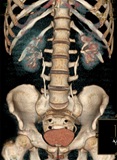

- T.A.C. (Escáner)

Es una prueba no invasiva, pero más cara y menos accesible que las radiografías. La dosis de radiación (Rayos X) que se recibe es alta. Diagnostica muy bien problemas de los huesos y menos de los tejidos adyacentes. En la actualidad se pueden obtener imágenes en 3 dimensiones que nos ayudan a comprender mejor el estado de las vértebras. Puede utilizarse como guía para obtención de biopsias, cultivos, etc. Su uso se reserva al médico hospitalario.